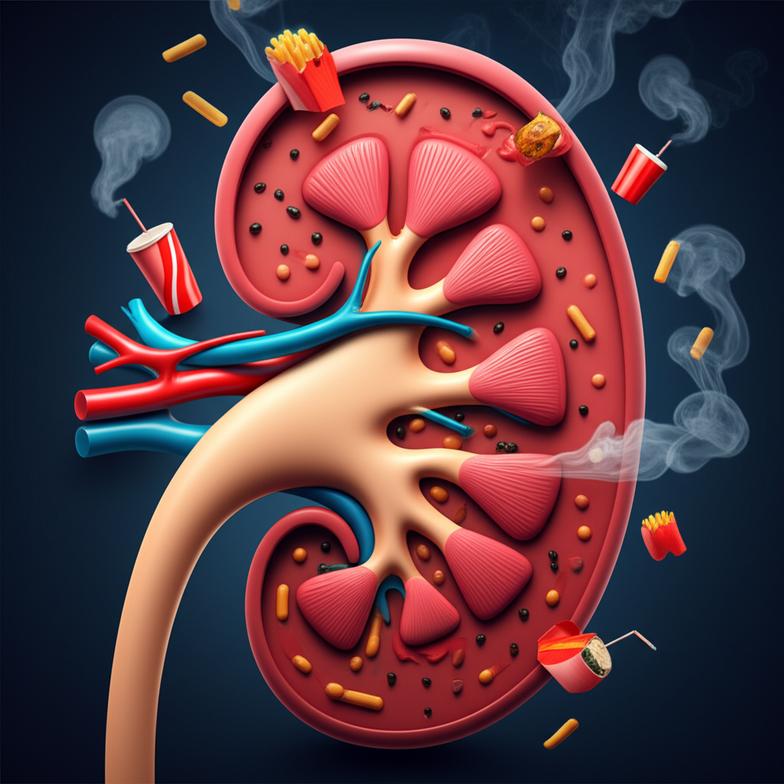

ปัจจัยเสี่ยงด้านโภชนาการและไลฟ์สไตล์: ตัวการทำลายไต

ในมุมมองของเวชศาสตร์ชะลอวัย เรามุ่งเน้นการค้นหาสาเหตุรากฐานของความเสื่อม ซึ่งสำหรับไตแล้ว ปัจจัยเสี่ยงจากโภชนาการและไลฟ์สไตล์มีบทบาทอย่างยิ่งต่อการเกิดและดำเนินของโรคไตเรื้อรัง การหลีกเลี่ยงหรือปรับเปลี่ยนปัจจัยเหล่านี้จึงเป็นหัวใจสำคัญของการดูแลเชิงป้องกัน

สาเหตุหลักๆ ที่มักพบได้แก่:

- การบริโภคอาหารรสเค็มจัด: โซเดียมที่มากเกินไปทำให้ร่างกายต้องทำงานหนักขึ้นเพื่อขับออก ส่งผลให้ไตต้องทำงานหนักและอาจนำไปสู่ความดันโลหิตสูง ซึ่งเป็นสาเหตุสำคัญของโรคไต

- การบริโภคน้ำตาลและอาหารแปรรูปสูง: การบริโภคน้ำตาลในปริมาณมากเป็นประจำไม่เพียงแต่เพิ่มความเสี่ยงเบาหวาน ซึ่งเป็นสาเหตุอันดับหนึ่งของโรคไต แต่ยังกระตุ้นการอักเสบในร่างกายและเพิ่มภาระให้ไต

- ขาดการออกกำลังกาย: การมีกิจกรรมทางกายไม่เพียงพอส่งผลต่อภาวะอ้วน ความดันโลหิตสูง และเบาหวาน ซึ่งล้วนเป็นปัจจัยเสี่ยงต่อไต

- ความเครียดเรื้อรัง: ความเครียดส่งผลต่อการทำงานของระบบฮอร์โมนและกระตุ้นการอักเสบ ซึ่งมีผลกระทบต่ออวัยวะภายใน รวมถึงไตด้วย

- การดื่มน้ำไม่เพียงพอ: การขาดน้ำเป็นประจำทำให้เลือดมีความเข้มข้นสูงขึ้น ไตต้องทำงานหนักขึ้นในการกรองของเสีย และเพิ่มความเสี่ยงต่อการเกิดนิ่วในไต

ความดันโลหิตสูงและเบาหวานที่ไม่สามารถควบคุมได้ ถือเป็นสองปัจจัยเสี่ยงที่สำคัญที่สุดที่นำไปสู่โรคไตเรื้อรัง การดูแลควบคุมโรคประจำตัวเหล่านี้จึงเป็นกุญแจสำคัญในการรักษาสุขภาพไต การตระหนักถึงพฤติกรรมเหล่านี้และค่อยๆ ปรับเปลี่ยนจะช่วยลดภาระของไตและชะลอความเสื่อมได้